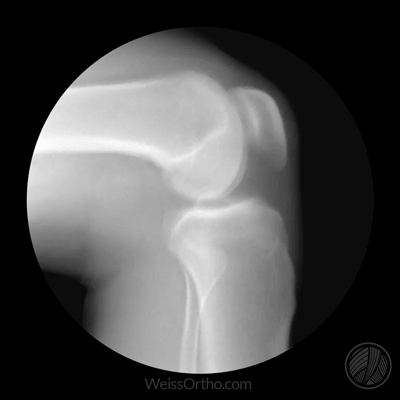

经查体并结合辅助检查,医生马三辉发现,小郑不仅左膝髌骨半脱位,同时还伴有左髌骨内、外侧支持带损伤、左股骨外侧踝碎片骨折等多处损伤。

髌骨就是我们通常说的“膝盖”,它就像河道里行驶的小船,而髁间窝就像河道,髌骨的内外侧支持带就像是小船的两只小桨,起到维持髌骨稳定的作用。正常情况下,“小船”在河道里行驶非常平稳,“船底”和“河道”之间的缝隙也是均等的。可当髌骨出现脱位或者半脱位时,“小船”就会翻向一侧,“船底”和“航道”的间隙一侧增大,一侧变小。间隙变小的一侧在运动中,受到的压力也就越大,就像小船触礁一样。“小船”的主人就会出现疼痛、肿胀、活动受限等相应的症状。

而此时的小郑,她的“小船”就出现了侧翻问题,同时“小船”的“双桨”也发生了损伤。这就需要医护人员及时帮小郑把侧翻的“小船”以及“船桨”都修复好,好让“小船”继续正常航行。